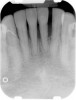

Figure 4  Radiograph of oral bisphosphonate user.

Under the sextant approach, one quadrant is treated and the patient is left to heal for 2 months before proceeding to any additional quadrants. While the patient heals, a 10-day course of antibiotics and 2 months of twice-daily chlorhexidine rinsing may be prescribed. Figure 4 shows a patient who was taking oral bisphosphonates for 3 years and was treated with the sextant approach. As seen in the radiograph, the patient has one molar in the lower right quadrant. This tooth was extracted and the patient was given 2 months to heal (Figure 5 and Figure 6). The patient was placed on antibiotics and chlorhexidine rinse. After 2 months, no signs of BRONJ were observed, and the anterior teeth were scheduled for extraction. They were extracted as atraumatically as possible, and the site was sutured (Figure 7 and Figure 8). The patient then was given another 2 months to heal, following the previous protocol. After 2 months of healing, no BRONJ was observed (Figure 9). The patient was able to move forward with the prosthesis.